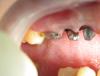

Ст@ся Опубликовано 8 августа, 2013 Поделиться Опубликовано 8 августа, 2013 Запилено под десну. прилегание вкладок не очень Ссылка на комментарий

k.t.m. Опубликовано 8 августа, 2013 Поделиться Опубликовано 8 августа, 2013 6 -ка дистально не доработана,вкладки и культя не полированы -для слепка плохо,глубокий запил с вашей стороны,со стороны техника прилегание не очень судя по толщине цемента Ссылка на комментарий

k.t.m. Опубликовано 9 августа, 2013 Поделиться Опубликовано 9 августа, 2013 Понятно! Значит если Бобби был таким в 2001 году значит я иду по графику!)) Ну я очень надеюсь что вы мне поможете!)И еще пару фото!)радует ,что зубы витальные)))перед оттиском нить бы я вытащил, и я не представляю как вы туда ее поставили при таком глубоком препе и еще гинги-пак? 1 Ссылка на комментарий

PLAY Опубликовано 9 августа, 2013 Поделиться Опубликовано 9 августа, 2013 очень глубокий запил, олд скул Ссылка на комментарий

ходок Опубликовано 10 августа, 2013 Поделиться Опубликовано 10 августа, 2013 (изменено) Я имел ввиду что под десну часто работают с целью скрыть плохое прилегание каркасов к уступу (разумеется с нарушением эстетики). А почему оно плохое - несколько вариантов. Не вижу зла на жевательной группе на уровне с десной. До сих пор есть техники, работающие без увеличения! По фото судя выбрана вся борозда и ретракция невозможна в принципе (без разрывов) Изменено 10 августа, 2013 пользователем ходок Ссылка на комментарий